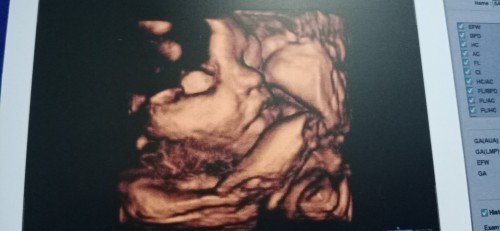

อ้าปากหวอเลย55

จมูกพุ่งจังลูก